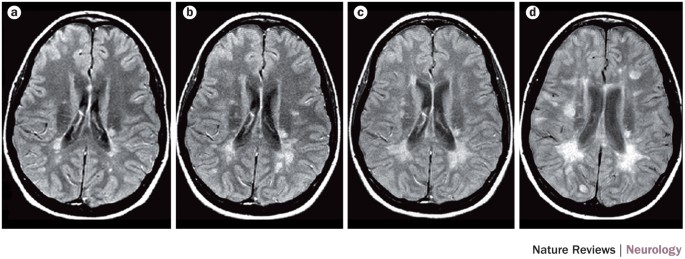

View Multiple Sclerosis Brain Mri Images. Mri studies of multiple sclerosis: Multiple sclerosis (ms) is a condition in which the body's immune system attacks the protective covering (myelin) surrounding the mri can reveal telltale areas of damage called lesions, or plaques, on the brain or spinal cord.

Bear in mind that a normal mri does not ensure that a person does not have ms. Multiple sclerosis and mri basics: Mri, which can reveal areas of ms (lesions) on your brain and spinal cord.

An mri identifies scarring or lesions in the brain and spinal cord. In ms, the immune system attacks and damages or destroys myelin, a substance that surrounds and insulates the nerves. Segmentation of multiple sclerosis lesions from mr brain. Frederik barkhof, robin smithuis and marieke hazewinkel.